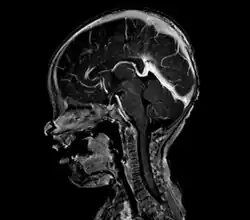

vein of Galen malformation

A cerebral AVM diagnosis is established by neuroimaging studies after a complete neurological and physical examination.[5][13] Three main techniques are used to visualize the brain and search for an AVM: computed tomography (CT), magnetic resonance imaging (MRI), and cerebral angiography.[13] A CT scan of the head is usually performed first when the subject is symptomatic. It can suggest the approximate site of the bleed.[3] MRI is more sensitive than CT in the diagnosis, and provides better information about the exact location of the malformation.[13] More detailed pictures of the tangle of blood vessels that compose an AVM can be obtained by using radioactive agents injected into the blood stream. If a CT is used in conjunction with an angiogram, this is called a computerized tomography angiogram; while, if MRI is used it is called magnetic resonance angiogram.[3][13] The best images of a cerebral AVM are obtained through cerebral angiography. This procedure involves using a catheter, threaded through an artery up to the head, to deliver a contrast agent into the AVM. As the contrast agent flows through the AVM structure, a sequence of X-ray images are obtained.[13]